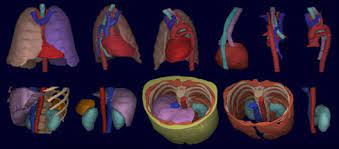

의료 영상처리는 의학 분야에서 매우 중요한 역할을 합니다. 이 분야에서는 CT, MRI, X-ray, 초음파 등의 영상 데이터를 처리하고 분석하여 질병 진단, 치료 및 예방 등에 활용됩니다.

이미지 처리 기술을 이용한 의료 영상 분석은 정확한 진단 및 예측을 위해 매우 중요합니다. 이를 위해 다양한 이미지 처리 기술들이 개발되어 왔습니다. 이러한 기술들은 대개 이미지의 전처리, 분할, 분류, 추적 등의 작업에 활용됩니다.

예를 들어, CT 영상 분석에서는 엣지 검출, 분할, 특징 추출, 객체 검출 등의 작업을 수행합니다. 또한, MRI 영상 분석에서는 뇌 성분 분할, 종양 감지, 질환 진단 등에 활용됩니다. 또한, 딥러닝 기술을 이용한 의료 영상 분석은 최근에 많은 연구가 진행되고 있습니다.

3D Slicer: 의료 영상 처리 및 분석을 위한 고품질 오픈소스 플랫폼입니다.